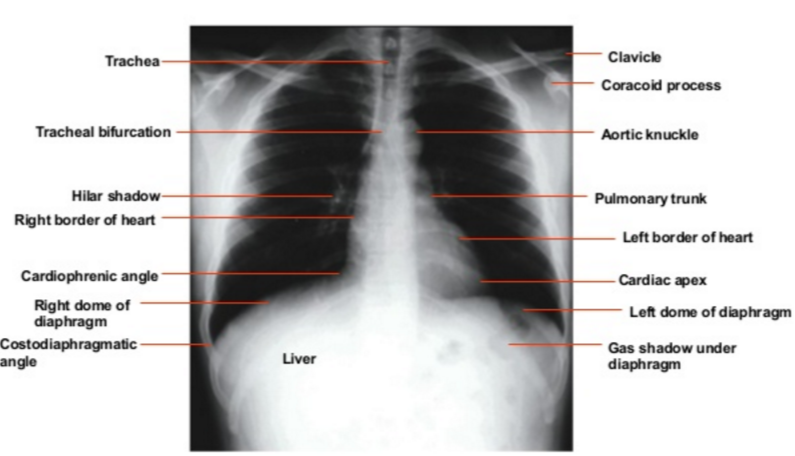

正常な肺門陰影はどう見えるか

肺門陰影は左右に見られるが、共に形はくぼんでいて、大きさ濃度は左右同じ程度である。位置は左の肺門が右に比べて僅かに高いところにある(これは左肺動脈が解剖学的に右肺動脈よりも高い所にあることに由来する。)

下葉の肺動脈は肺門部から下の方に伸びていて、大きさは手の小指と同じぐらいである(下の写真参照)。健常人の胸部レントゲンにおいて右の肺門陰影では94%、左の肺門陰影は62%が小指様(little finger )の所見に見えるという報告もある。

正常な肺門陰影の写真その2